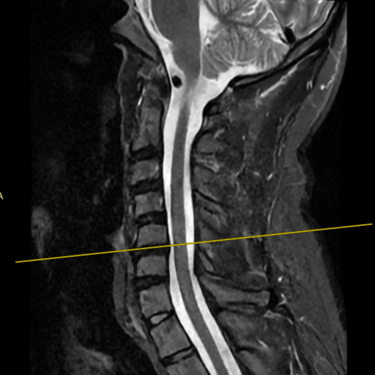

Discopatía Cervical con Inestabilidad de Columna | Diagnóstico por Resonancia Magnética

La discopatía cervical con inestabilidad de columna es una patología que compromete la movilidad y estabilidad de la región cervical, generando síntomas como dolor cervical crónico, rigidez, irradiación a miembros superiores y, en casos avanzados, déficit neurológico. La resonancia magnética (RMN) es el método diagnóstico de elección, ya que permite evaluar la degeneración discal, protrusiones o hernias discales, cambios en los cuerpos vertebrales, compresión radicular y signos de inestabilidad. Su precisión ayuda a planificar el tratamiento más adecuado, que puede incluir manejo conservador o cirugía, según la gravedad y el compromiso neurológico del paciente.